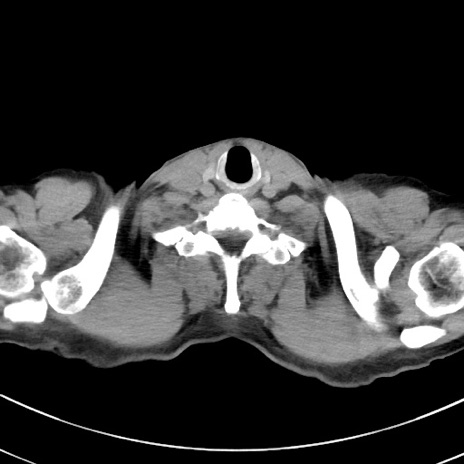

症例38(横断像)

【症例】70歳代 男性

【主訴】腹痛・嘔吐

【現病歴】昨晩より、嘔吐・腹痛あり。今朝になっても嘔吐あり。来院。

【既往歴】心臓バイパス手術、開腹胆摘、腸閉塞

【身体所見】BP 107/71mmHg、HR 116/min、腹部:平坦、軟、下腹部に軽度圧痛あり。反跳痛なし。

【データ】WBC 15100、CRP 0.32